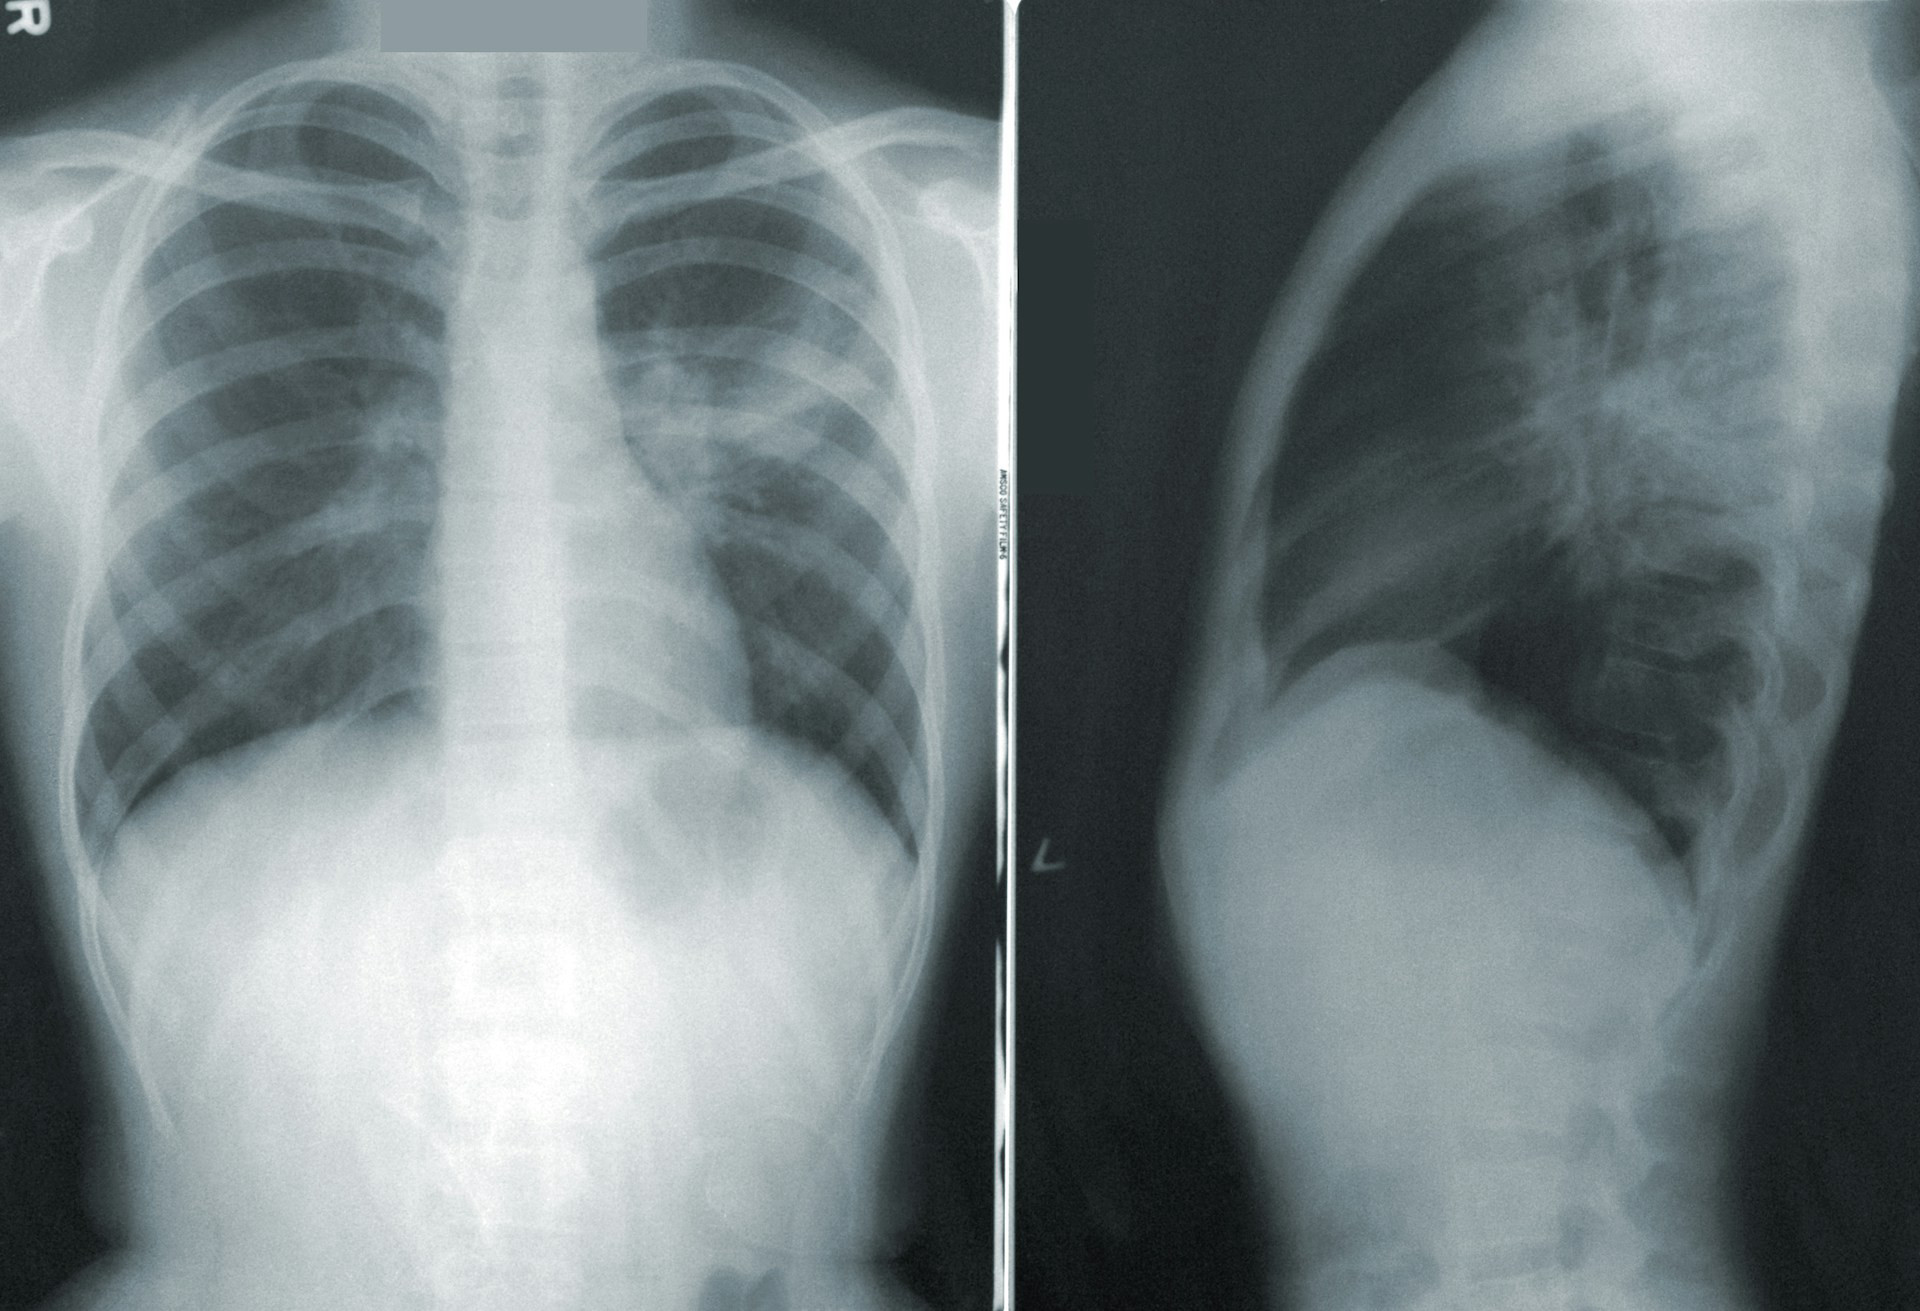

A co, jeśli powiem Wam, że wizja ze świata Cyberpunka spełnia się właśnie dziś? Amerykańscy chirurdzy usunęli pacjentowi oba płuca — i utrzymali go przy życiu przez dwie doby, używając w pełni funkcjonalnego, sztucznego odpowiednika. Medycyna przyszłości, cybermedycyna, medtech: zwał, jak zwał. To niesamowite, do czego jesteśmy zdolni, dzięki ogromnemu postępowi w technologiach i medycynie.